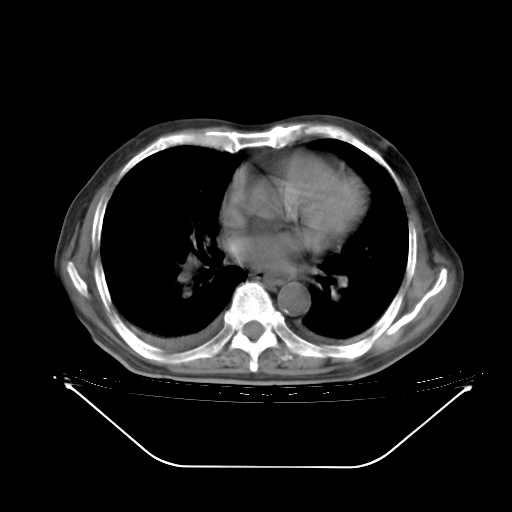

今天复查肺部CT,发现双肺广泛磨玻璃样改变。所以我把3月19日和5月9日相隔50天的肺部CT上传。请大家会诊。

5月9日肺部CT(在4月27日齐鲁医院肺部CT描述部分肺组织磨玻璃样改变,12天后肺组织广泛磨玻璃样改变)

2009年5月9日肺部CT

大致读了系列胸部CT:纵隔窗无明显异常,肺窗:从4、27至今:主要是双肺中下野外带可见毛玻璃样改变,目前处于急性肺泡炎阶段,至于原因考虑1、结替组织或胶原血管性疾病所致?2、恶性疾病如恶组在肺部所致的表现或细支气管肺泡癌?3、药物或其它原因如肺蛋白沉着症所致肺泡炎目前不太可能?总之,明天就去请我院的呼吸科、感染科、血液科和临免专家会诊哈。